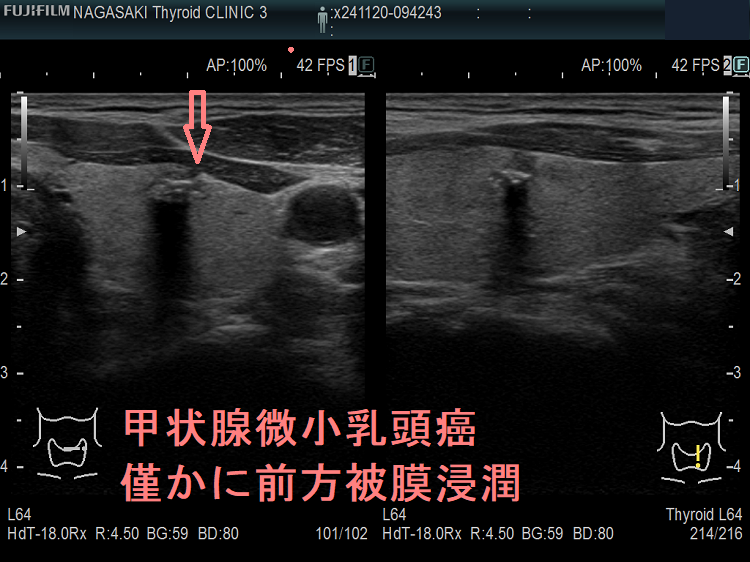

- 被膜浸潤した甲状腺微小乳頭癌 超音波(エコー)画像

ケース⑤ 甲状腺微小乳頭癌 僅かに前方被膜浸潤